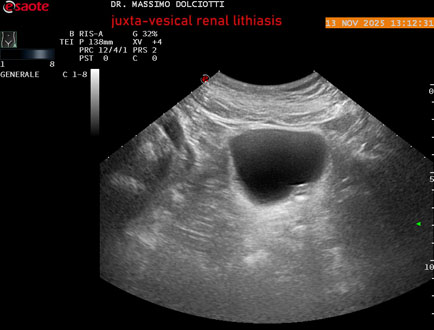

Data inserimento: 14/11/2025

Ecografia del: 13/11/2025

Strumento: Esaote MyLab Eight

Sonda: Convex Multifrequenza 1-8 MHz

Età Paziente: M 59 anni

Motivazione dell'esame: dolori al basso addome ed al fianco sinistro, comparsi la notte precedente.

Commento all'esame: le immagini ed il video documentano al rene sinistro, idronefrosi di 1°-2° grado, con presenza di immagine iperecogena, con cono d'ombra posteriore, allo sbocco dell'uretere sinistro, in sede iuxta-vescicale, delle dimensioni di 6,2 mm, con segno del Twinkling Artifact (o segno di Arlecchino), da ricondurre a litiasi.

Conclusioni: litiasi renale sinistra iuxta-vescicale (left juxta-vesical renal lithiasis).